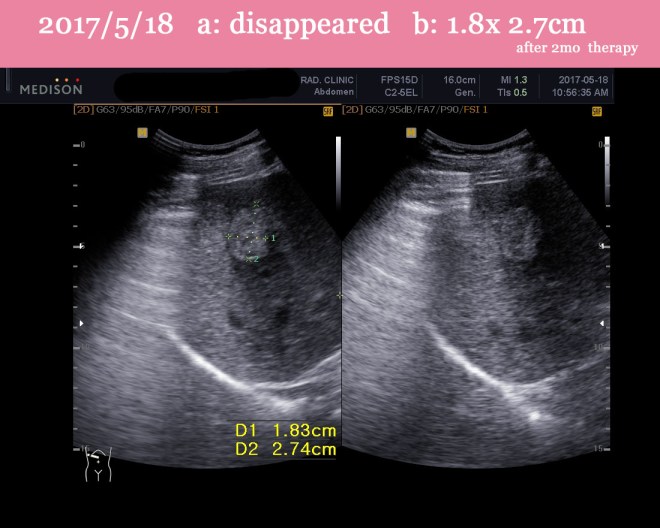

- 2017년 5월 18일 두개의 종양 중에 하나는 소실됨. 또 하나는 면적대비 58 %로 감소됨

- 현재 한방 단독요법으로 치료 지속 중인 환자임

| 2017/5/18 | ABDOMINAL SONOGRAM : Comparison with2017-03-30

1. Known HCC, post-TACE state 2. Previously noted an irregular hyperechoic lesion in the right hepatic lobe is seen again with more regression; (2.7 x 3.2cm ->1.8 x 2.8cm). Previously noted another hypoechoic lesion is not identified in this study. |

초음파 검사

두개 중에 하나는 없어지고 작은 것은 줄어들음 |

3. 치료 두달 뒤 (2017/5/18) ABDOMINAL SONOGRAM : Comparison with2017-03-30

- Known HCC, post-TACE state

- previously noted an irregular hyperechoic lesion in the right hepatic lobe is seen again with more regression; (2.7 x 3.2cm ->1.8 x 2.8cm).

- Previously noted another hypoechoic lesion is not identified in this study.